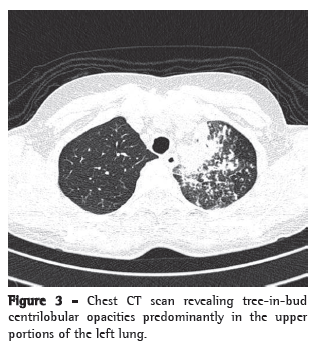

The patient stated that she was not a smoker or an alcoholic. She reported that she had tested negative on a tuberculin skin test (TST) conducted before the initiation of adalimumab treatment, and that, according to the rheumatologist who treated her, a chest X-ray performed at the time was normal. After the use of azithromycin (three and half months prior), she also received an additional infusion of adalimumab. Physical examination revealed mild pallor and no palpable lymph node enlargement. There were fine rales in the upper third of the left hemithorax and coarse rales in the middle third of the right hemithorax, as well as scattered rhonchi. Her hands and feet had joint deformities. A chest X-ray revealed alveolar opacities in the left upper lobe, left lower lobe and middle lobe, as well as images suggestive of bronchogenic dissemination (Figure 2). A CT scan of the chest revealed tree-in-bud centrilobular opacities (Figure 3).